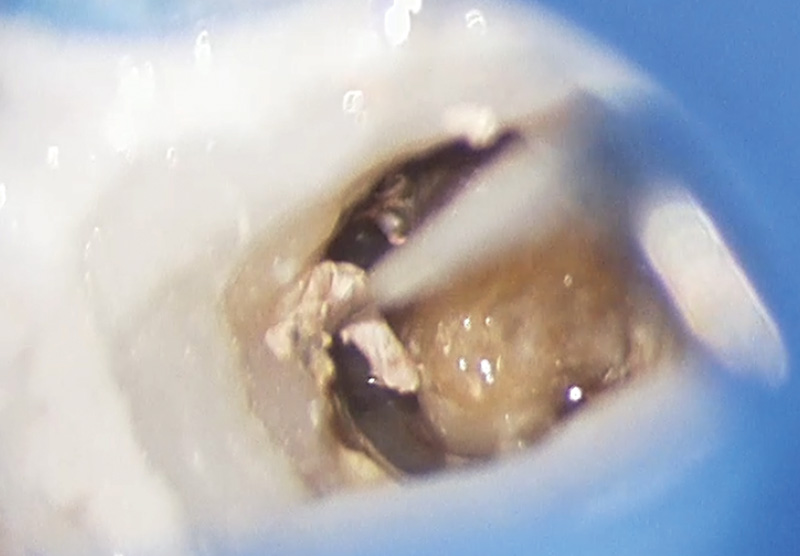

![[写真] 浮腫性の炎症が続き、触るとすぐに出血する](/academic/dentalmagazine/wp-content/uploads/sites/2/2025/11/195-3_photo09.jpg)

浮腫性の炎症が続き、触るとすぐに出血する。少量の次亜塩素酸ナトリウムを入れ、通電させると発熱が起こり、根尖孔の組織を蒸散できる。 -